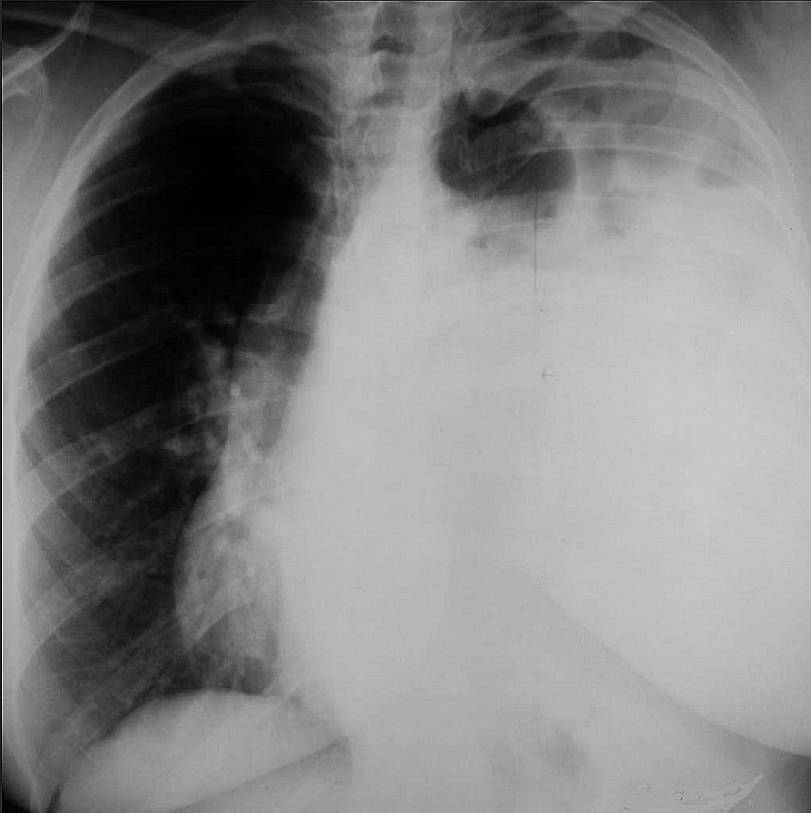

Patient with Severe Pneumonia Post category:Spot Diagnosis Post published:May 6, 2024 Share on Facebook Share on X (Twitter) Share on Pinterest Share on Email Share on Reddit Patient with Severe Pneumonia A 72-year-old female patient had a severe pneumonia and she underwent thorough imaging. She suffered from frequent respiratory infections (usually not severe) but had never had any kind of accident. What’s the diagnosis ? FULL CASE AND ANSWER Share on Facebook Share on X (Twitter) Share on Pinterest Share on Email Share on Reddit Read more articles Previous PostDouble Vision and Eyelid Drooping Next PostLong-Standing, Painful Deformation of the Right Tibia You Might Also Like Chest X-Ray in patient 1 week after the onset of chest pain November 26, 2021 Pain and Swelling of the Left Thigh and Lower Leg September 4, 2022 Well-demarcated Tan-colored Patch Covered with Coarse Dark Hairs July 16, 2022